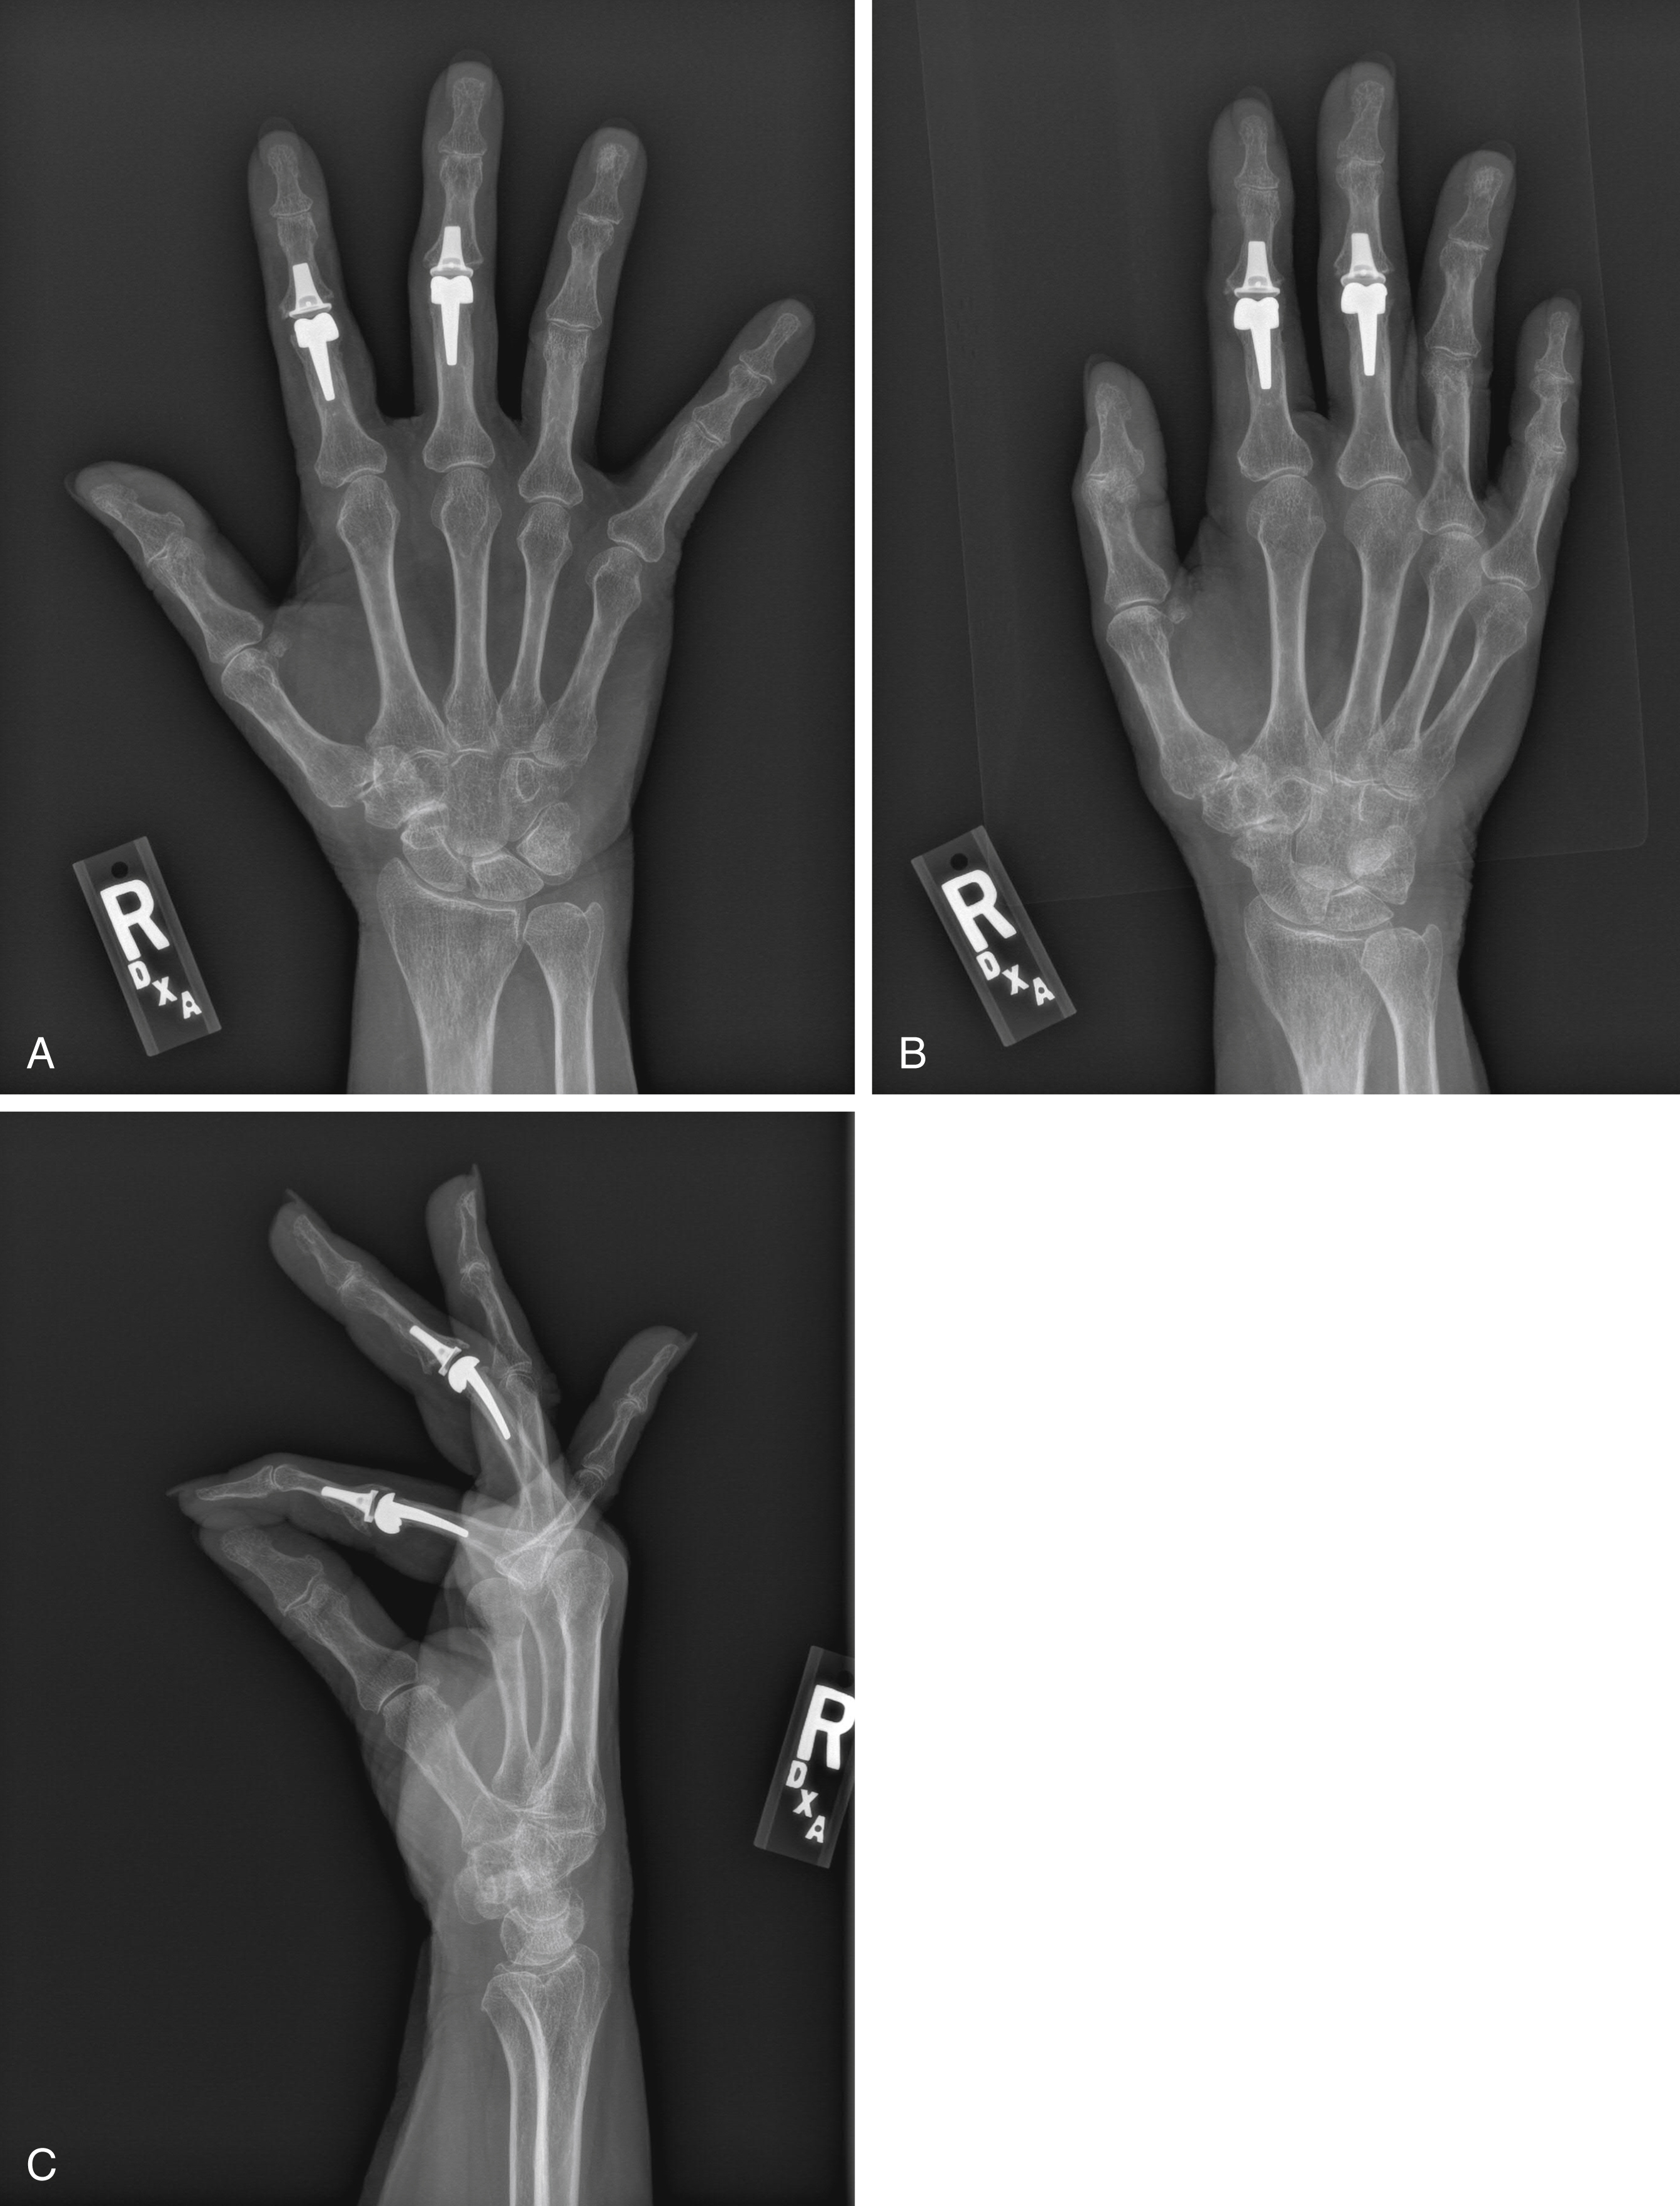

SRA implant arthroplasty ( Fig. 57.3 ) is also a nonconstrained device that was designed by Ronald Linscheid based on his analysis of anthropomorphic data determined from cadaveric specimens. Murray et al followed 47 patients that had 67 prostheses, with a mean follow-up of 8.8 years finding 59/67 joints still in service at follow-up with a cumulative failure rate of 16% at 15–25 years. The authors found no association of failure, radiolucency surrounding the implant or subsidence of the implant whether cement was or was not used. There was also no association of implant failure based on the diagnosis of OA or RA. There were 22 complications among 14 patients. There were no infections. The authors concluded that this modality of arthroplasty is a reliable option to address pain and deformity, both in osteoarthritis and in rheumatoid arthritis.